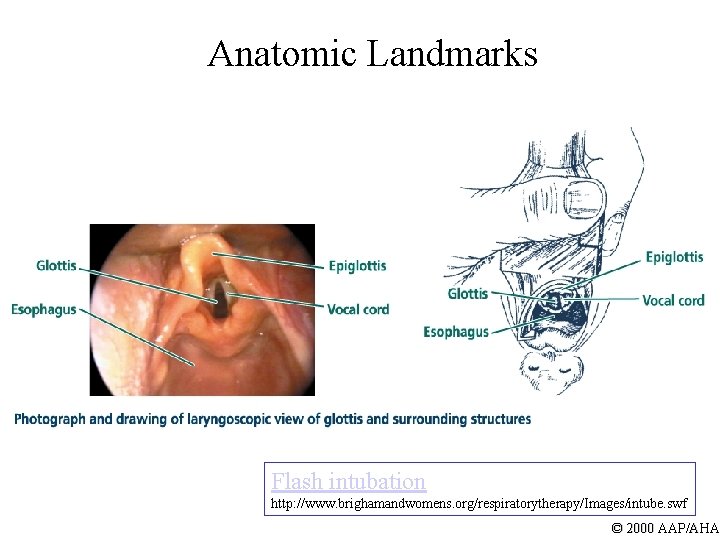

Anatomic Landmarks Flash intubation http: //www. brighamandwomens. org/respiratorytherapy/Images/intube. swf © 2000 AAP/AHA

Visualize Landmarks l Vocal cords appear as vertical strips or as inverted letter “V” l Downward pressure on cricoid may help bring glottis into view l May need to suction secretions © 2000 AAP/AHA